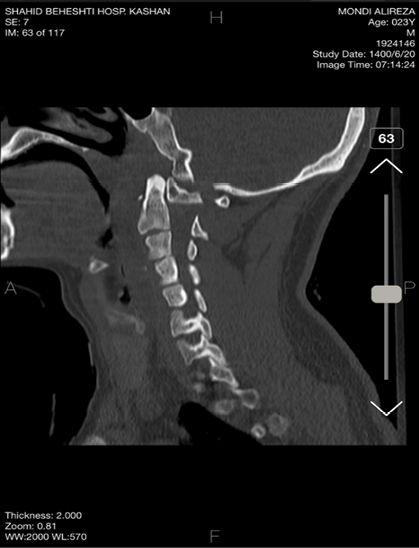

A 23-year-old Iranian gentleman was admitted to Shahid-Beheshti Hospital of Kashan and was hit by a Motor-to-Barrier Accident. He was fully conscious and oriented with a normal level of consciousness and was treated according to the Advanced Trauma Life Support Protocol. He was hemodynamically stable and experiencing mild respiratory distress due to cervical edema and tenderness. On examination, he had cervical tenderness (C1-C2) and a GCS of 15/15, pupils were symmetrical and reactive to light, and movement was normal in four extremities. There was no swelling or laceration in the scalp; however, tenderness in the neck was detected. The physical examination showed no neurological deficits, neither motor nor sensory. He had cervical motion and rotation limitations. His Deep tendon Reflexes were normal. A CT scan revealed a posterior subluxation of the odontoid process lay in front of the atlas anterior arch with no associated fractures and disruption of the spinolaminar line (Figure-1). No intracranial hemorrhage or midline shift was seen.

Figure 1. Pre-operative cervical CT scan shows posterior subluxation of the odontoid process lying in front of the anterior arch of the atlas, with no associated fractures or disruption of the spinolaminar line.